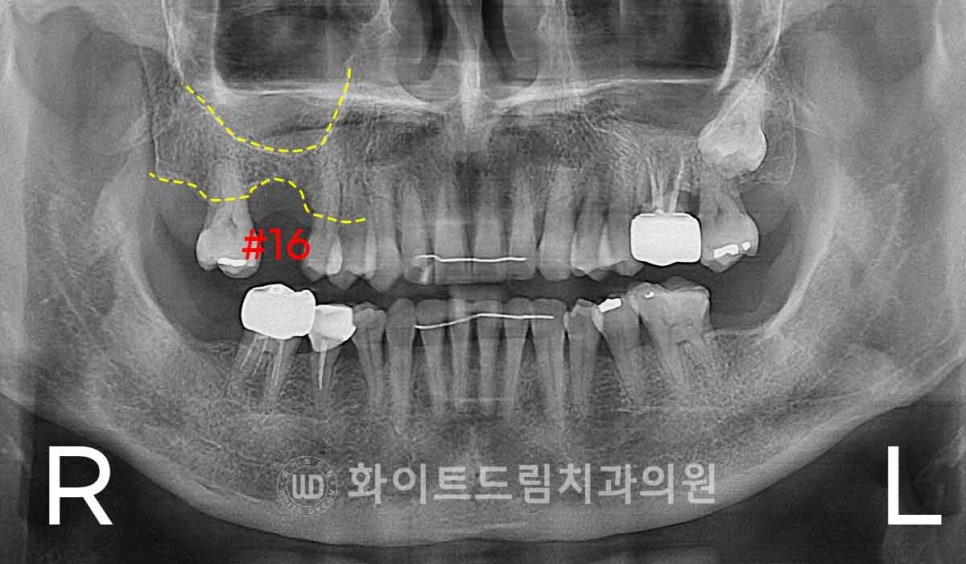

오늘 준비한 케이스도 이런 문제로 인해 16번 치아를 발치하신 뒤

방치를 하셔서 결국 잇몸 함몰까지 나타난 상태로 내원을 하셨던 환자분인데요.

상악동이 크게 내려온 경우는 아니었지만,

발치 후 협측 피질골(buccal cortical bone) 이 얇아지고 일부 흡수되면서

잇몸 볼륨이 부족해진 상태였습니다.

환자분의 경우 남아있는 잔존 잇몸뼈(치조골)의 높이가 약 3~4 mm 정도로 매우 낮아,

임플란트를 심을 경우 임플란트가 상악동 내부로 돌출될 위험이 있었습니다.

약 8–10 mm 정도의 임플란트를 안정적으로 식립하려면

최소한 상악동을 5 mm 이상 거상해야 했기 때문에,

측방 접근법(Lateral window sinus lift)을 이용해 수술을 진행했습니다.